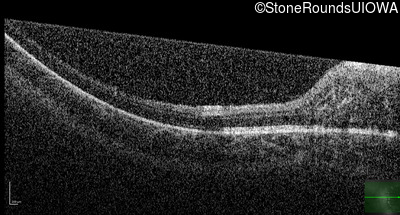

Optical Coherence Tomography - Right - 20/400

Exemplar

Optical Coherence Tomography - Left - 20/100

Exemplar / OCT Stack